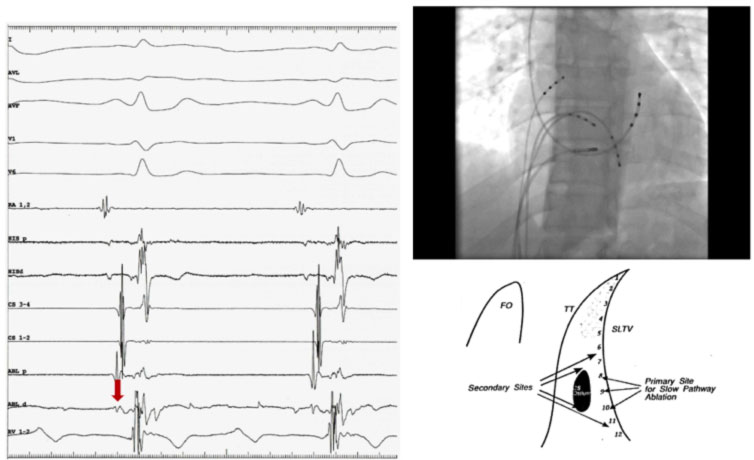

Nel caso in cui si voglia procedere al mappaggio della via lenta il catetere ablatore viene mosso accuratamente lungo l’anulus tricuspidalico alla ricerca del potenziale di via lenta che rappresenta la depolarizzazione della stessa. Nell’ ECG endocavitario il potenziale di via lenta si localizza tra la deflessione atriale e la deflessione ventricolare. Quando il potenziale di via lenta viene identificato, vengono erogate radiofrequenze (RF) in prossimità di tale sito. In caso di approccio anatomico invece vengono utilizzati i soli punti di repere fluoroscopici.

Generalmente la porzione di annulus tricuspidalico compresa tra l’ostio del seno coronarico ed il fascio di His viene suddivisa in tre segmenti: posteriore (vicino all’ostio del seno coronarico), medio, e anteriore (vicino al fascio di His). Il catetere viene posizionato lungo la valvola tricuspide e fatto scorrere finché non vengono registrati il potenziale atriale e quello ventricolare con la deflessione atriale più grande della deflessione ventricolare. A questo punto vengono erogate RF, e generalmente se la posizione del catetere è corretta è possibile osservare dei battiti giunzionali o una tachicardia giunzionale. Se dopo 10-15 secondi di RF non compaiono battiti giunzionali è bene interrompere l’erogazione e cambiare la posizione del catetere ablatore. Se al contrario compaiono i battiti giunzionali è bene erogare RF per altri 30-60 sec.